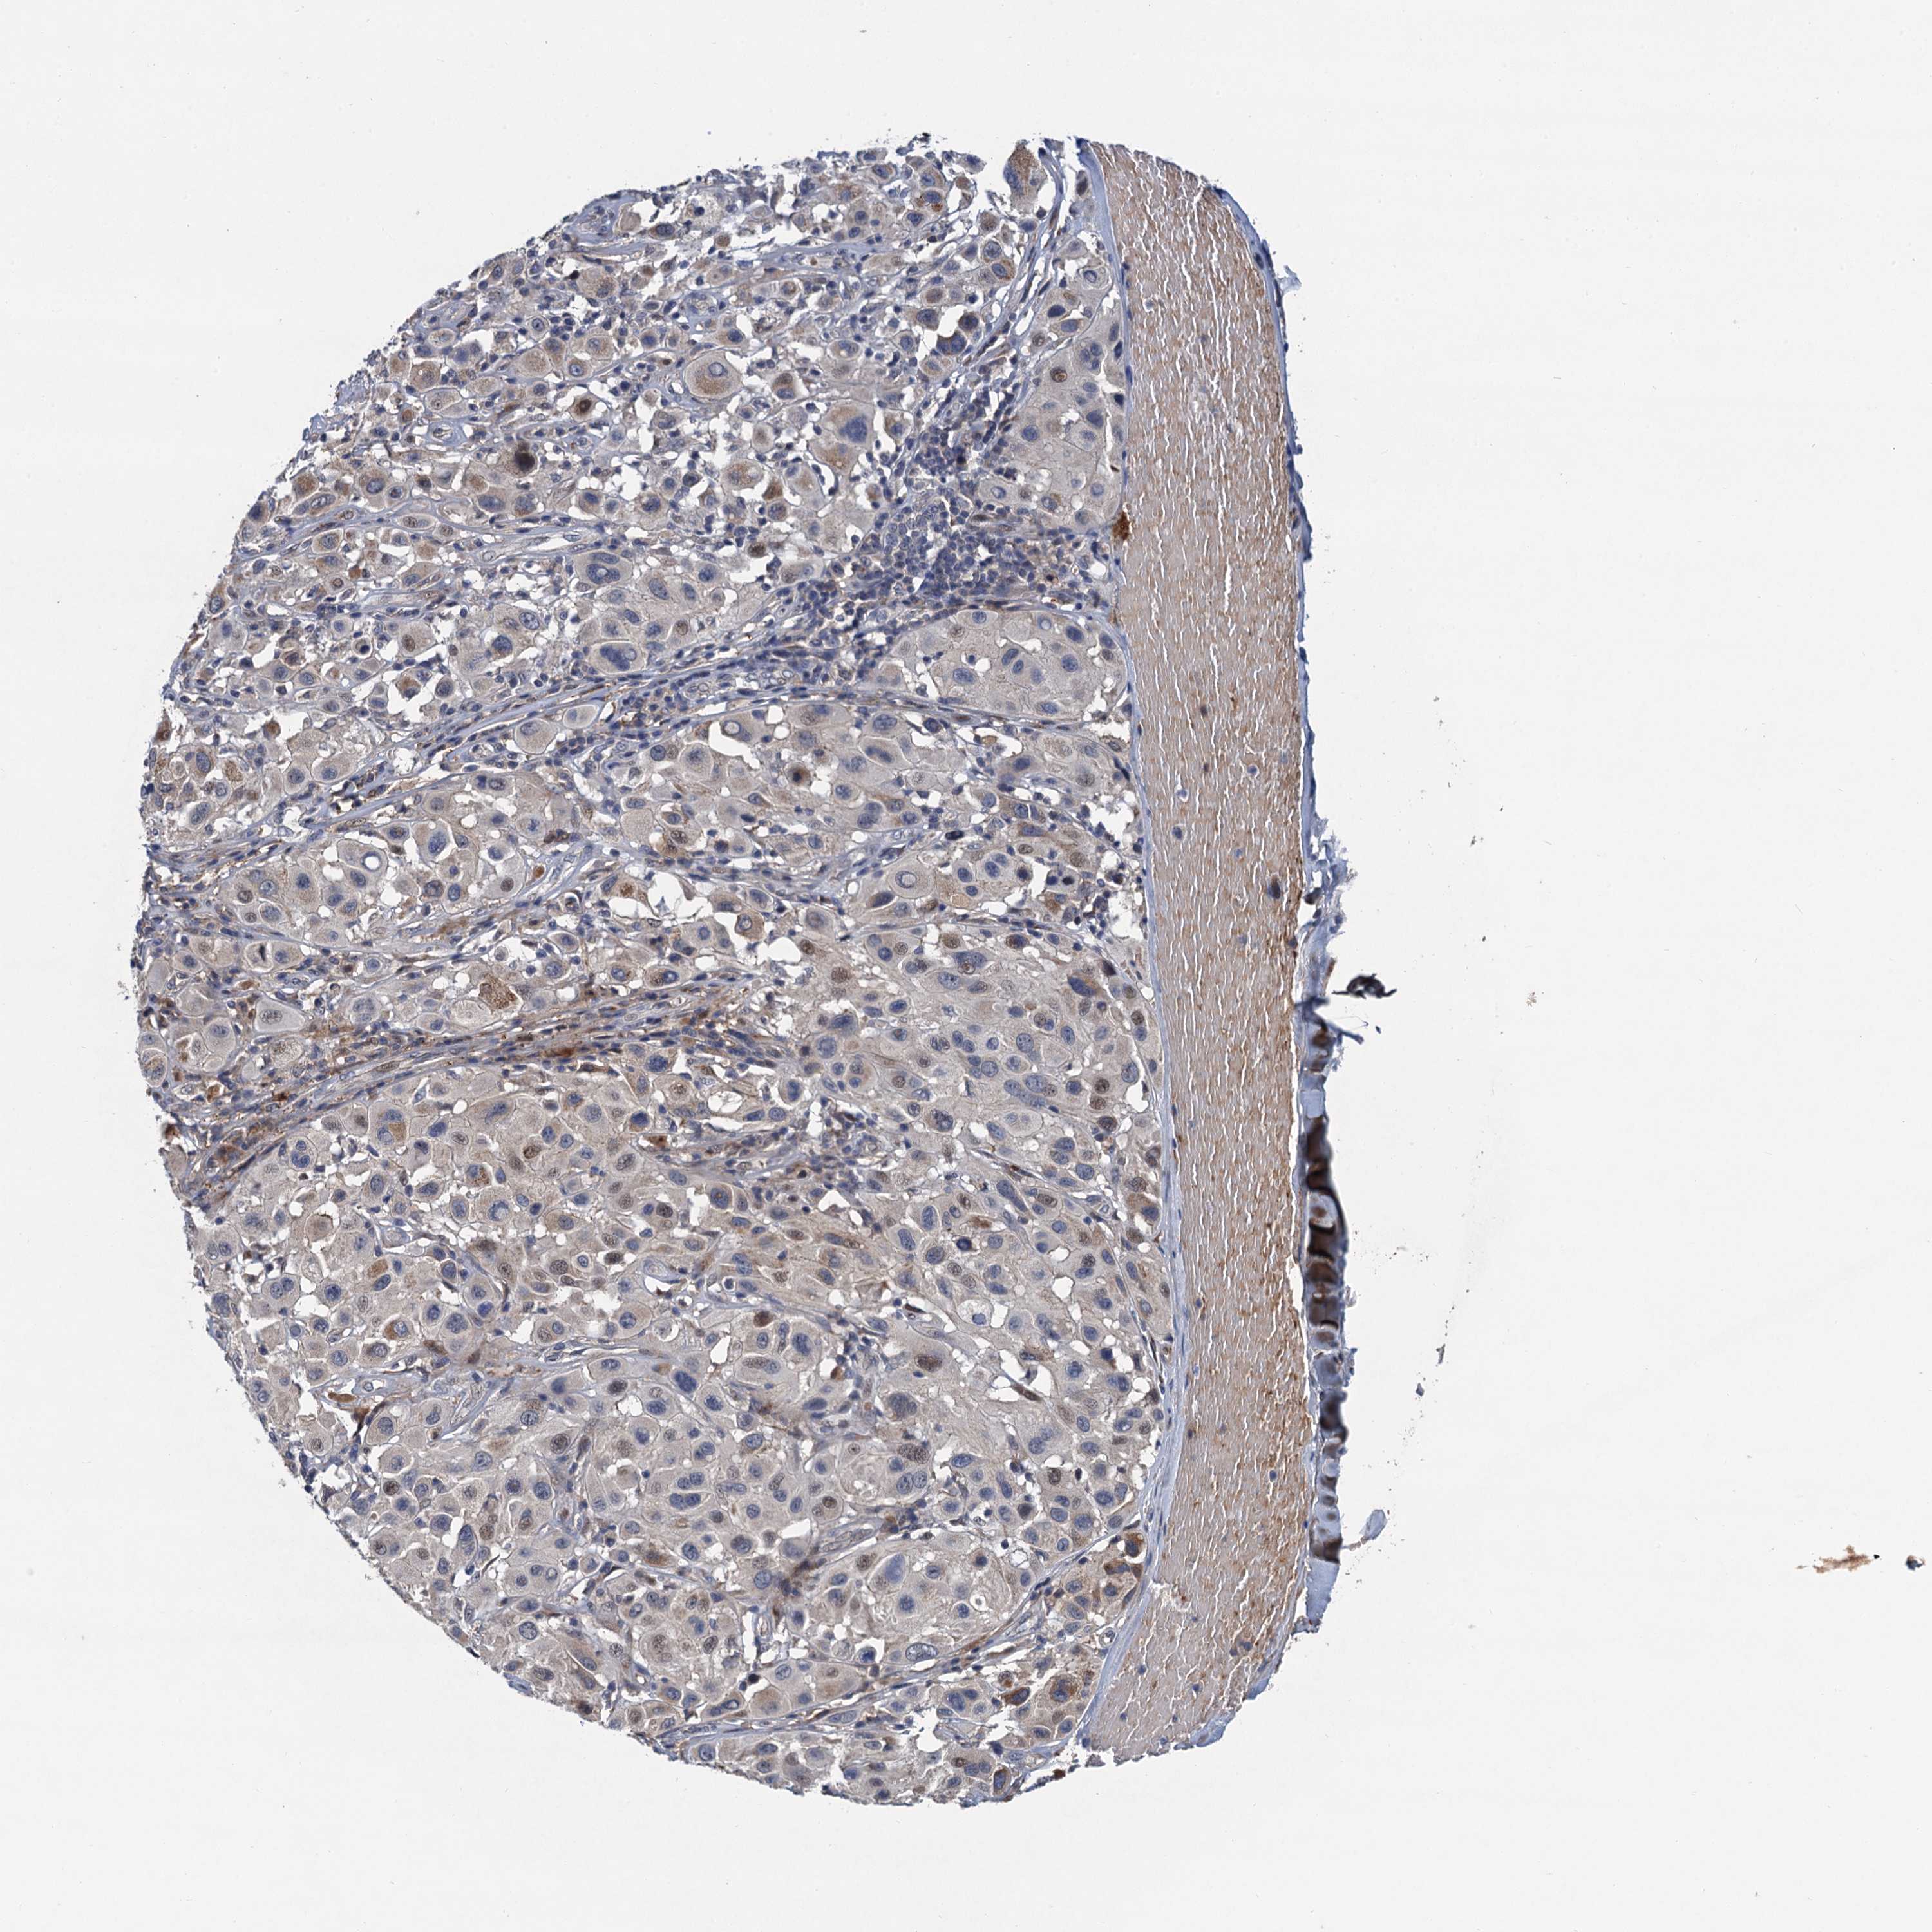

MELANOMA - Protein expressioni

A mouse-over function shows sample information and annotation data. Click on an image to view it in a full screen mode. Samples can be filtered based on level of antibody staining by selecting one or several of the following categories: high, medium, low and not detected. The assay and annotation is described here.

Note that samples used for immunohistochemistry by the Human Protein Atlas do not correspond to samples in the TCGA dataset.

Antibody stainingi

Antibody staining in the annotated cell types in the current human tissue is reported as not detected, low, medium, or high, based on conventional immunohistochemistry profiling in selected tissues. This score is based on the combination of the staining intensity and fraction of stained cells.

Each image is clickable and will lead to virtual microscopy that enables deeper exploration of all samples and also displays staining intensity scores, fraction scores and subcellular localization as well as patient and tissue information for each sample.

Antibody HPA041229

Staining

High

Medium

Low

Not detected

Intensity

Strong

Moderate

Weak

Negative

Quantity

>75%

75%-25%

<25%

None

Location

Nuclear

Cytoplasmic/membranous

Cytoplasmic/membranous,nuclear

Malignant melanoma, NOS

Malignant melanoma, Metastatic site